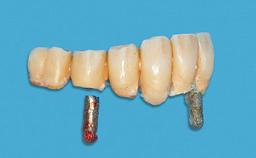

A 74-year-old male patient, a non-smoker, who had been wearing complete dentures for more than 30 years, presented to our clinic complaining about discomfort in connection with his lower denture. The patient suffered from asthma and had a history of cardiac disease and blood pressure disorders. All conditions were medically controlled and stable. The clinical inspection of the oral cavity revealed an ill-fitting complete mandibular denture. The patient expressed the wish for his lower denture to “stop moving when chewing, swallowing, and speaking.” He reported having heard about dental implants and asked whether these could help in “fixing” his lower denture, but also requested non-invasive treatment. The mucosa presented healthy and was free of defects such as pressure sores. An band of keratinized mucosa approximately 2 mm wide was visible. The patient’s mucosal biotype was medium thick to thin.